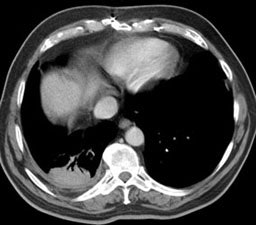

Computed Tomography: On CT the pleural thickening or calcification is clearly identified. Thickened lung markings and vessels swirl into the lesion which abuts the pleural surface ("comet tail sign"- central bronchovascular pedicle)- however, this finding may be absent in up to 8% of cases. Curvilinear air bronchograms are often visible within round atelectasis. The lesion is very commonly based or tethered by a strand to a thickened pleural surface. Pericicatril emphysema may also be seen. Volume loss within the affected lung is also common- often characterized by displacement of the fissure bounding the affected lobe. Calcification may also be found within areas of round atelectasis (up to 25% of cases)- possibly secondary to engulfment of a granuloma within the atelectatic lung, or invagination of a calcified pleural plaque. The lesion will enhance homogeneously after the administration of I.V. contrast (up to nearly 90% of cases). Inhomogeneous enhancement is atypical for rounded atelectasis [12].

Despite the ability of computed tomography to accurately identify features which are often associated with round atelectasis, it should be remembered, that the findings described above are not necessarily completely diagnostic for this entity. Other lesions can mimic these findings and rarely lung cancer can co-exist in an area of round atelectasis [12].

Round atelectasis on PET FDG imaging: The images below demonstrate the typical CT and FDG PET findings in round atelectasis. On CT, there are thickened lung markings and vessels which swirl into the lesion that abuts an area of pleural thickening. Note the lack of metabolic activity in round atelectasis on PET imaging. |